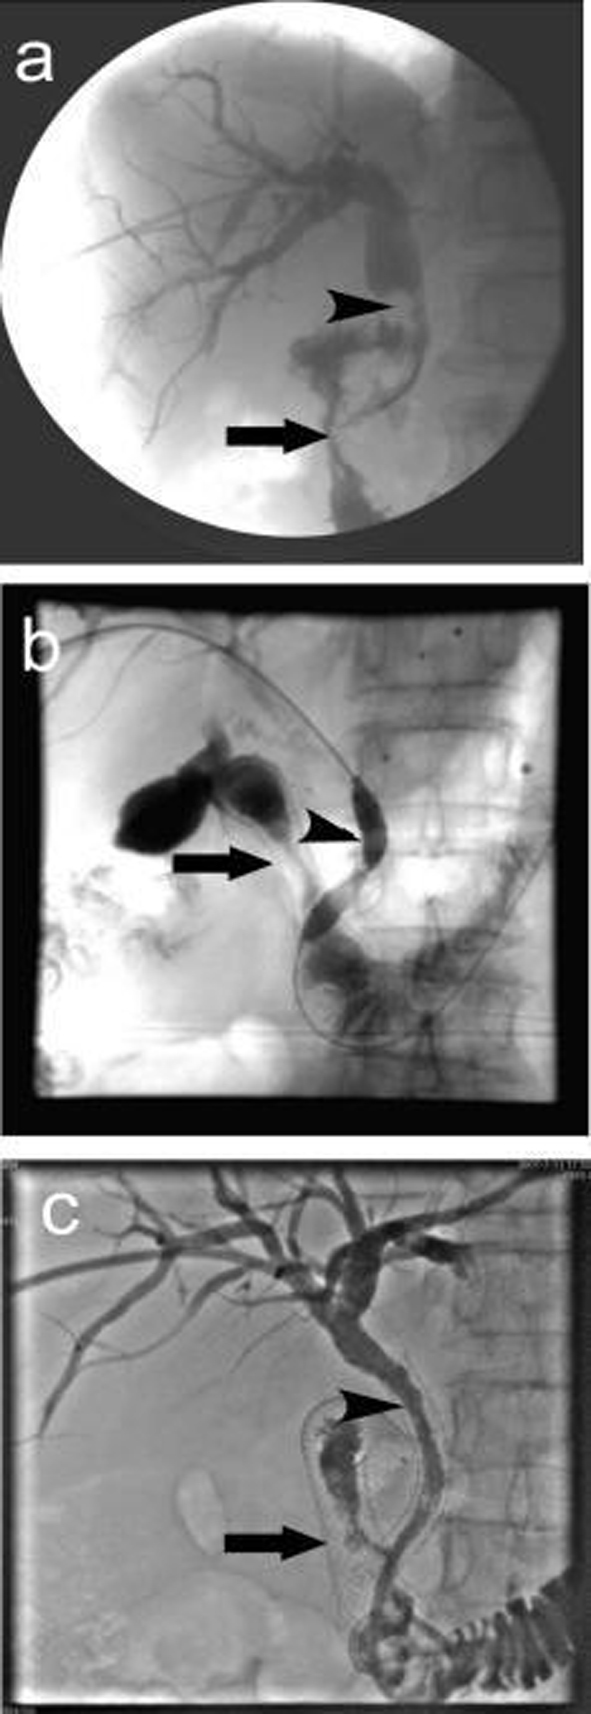

A total of 37 intestinal stents were placed in 32 patients, single stent was placed in 27 patients; in 5 patients, due to the long duodenal stenosis, double stents were placed in each patient. A total of 32 biliary stents were placed in 32 patients. The cholangiography 3 days after stenting proved patency of both intestinal and biliary stents, the success rate of combined intestinal and biliary stenting was 100%. Figure 1a shows the extrahepatic obstructive jaundice with biliary infection before stent placement, PTC revealed common bile duct lesions accompanied by duodenal stenosis. Figure 1b shows the biliary stenting following the intestinal stent was placed, PTCD was carried out to place the biliary stent. Figure 1c shows the biliary stent across the mesh of intestinal stent, the biliary and intestinal stents were both revealed patent. Figure 2 shows the relationship between biliary stent and intestinal stent.

![]() Click for large image | Figure 1. Procedure of double stenting. (a) Duodenal stenosis combined with common bile duct lesions. The arrow indicates descending duodenal stenosis, the arrow head shows the irregular contrast deficiency of lower common bile duct, which might be invaded by tumors which led to the expansion of common bile duct above the stenosis; (b) Biliary stent placement, the arrow shows duodenal stent, the arrow head shows balloon dilatation of common bile duct stenosis and the mesh of intestinal stent; (c) Biliary stent placement, the arrow shows duodenal stent, the arrow head shows biliary stent. The cholangiography showed both were patent. |